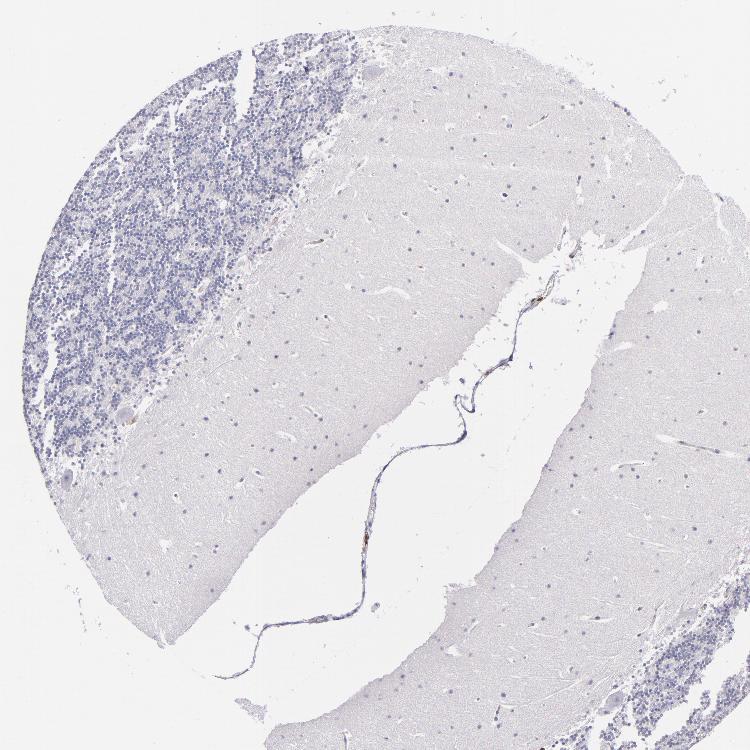

BRAIN CEREBELLUM Show tissue menu

CEREBELLUM - Expression summary

CEREBELLUM - Antibody stainingi

Antibody staining in the annotated cell types in the current human tissue is reported as not detected, low, medium, or high, based on conventional immunohistochemistry profiling in selected tissues. This score is based on the combination of the staining intensity and fraction of stained cells.

Each image is clickable and will lead to virtual microscopy that enables deeper exploration of all samples and also displays staining intensity scores, fraction scores and subcellular localization as well as patient and tissue information for each sample.

Antibody CAB002498

Purkinje cells Not detected

Cells in granular layer Not detected

Cells in molecular layer Not detected